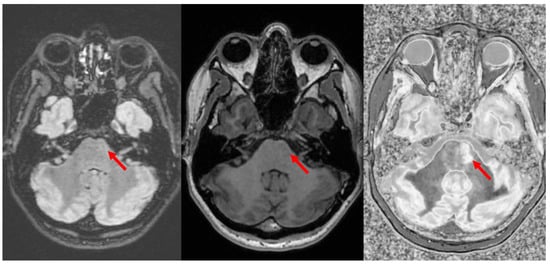

Figure 11.

Divided Subtracted Inversion Recovery (dSIR) in a patient with multiple sclerosis (MS). T2-FLAIR (left), inversion recovery (IR) T1-weighted (middle), and wide-domain dSIR with TIshort = 450 ms and TIlong = 850 ms (right) images through the pons in a patient with MS. A large plaque is obviously present in the left hemipons on the dSIR image (red arrow in the image on the far right). The contrast in this image is due to changes in white matter T1. The change in T1 is insufficient to cause noticeable contrast on the IR T1 image (middle). The change in T2 is insufficient to cause noticeable contrast on the T2-FLAIR image (left).